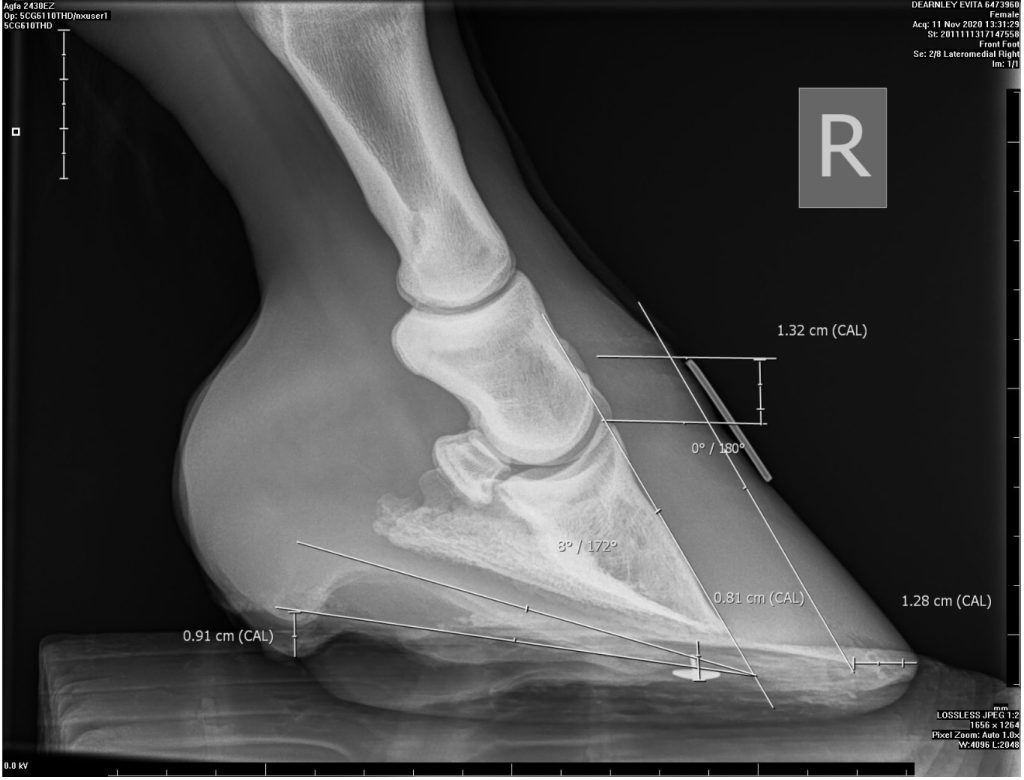

Changes to the internal hoof structures can be visible on x-rays and also on the outside of the hoof, such as with horizontal lines on the hoof wall. This can cause minor or severe issues depending on how much the coffin bone has rotated and/or descended.

Early intervention is key. The first and most important step is to call the vet and get them to come out if you suspect laminitis. They can then decide on the course of action. Your vet might suggest working with a good farrier or equine podiatrist to help make the horse more comfortable, as well as changes to diet and turnout (the focus of Part Two of this blog series). Further tests including X-rays may be taken after the acute phase, to check for rotation or distal descent.